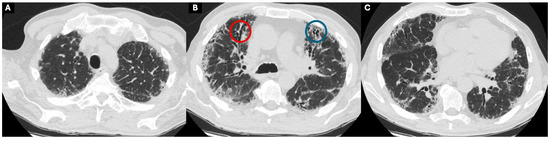

1.1. The Diagnosis and Evaluation of Patients with ILD in the ICU

- Charokopos, A.; Moua, T.; Ryu, J.H.; Smischney, N.J. Acute exacerbation of interstitial lung disease in the intensive care unit. World J. Crit. Care Med. 2022, 11, 22–32. [Google Scholar] [CrossRef]

- Collard, H.R.; Ryerson, C.J.; Corte, T.J.; Jenkins, G.; Kondoh, Y.; Lederer, D.J.; Lee, J.S.; Maher, T.M.; Wells, A.U.; Antoniou, K.M.; et al. Acute Exacerbation of Idiopathic Pulmonary Fibrosis. An International Working Group Report. Am. J. Respir. Crit. Care Med. 2016, 194, 265–275. [Google Scholar] [CrossRef]

- Suzuki, A.; Kondoh, Y.; Brown, K.K.; Johkoh, T.; Kataoka, K.; Fukuoka, J.; Kimura, T.; Matsuda, T.; Yokoyama, T.; Fukihara, J.; et al. Acute exacerbations of fibrotic interstitial lung diseases. Respirology 2020, 25, 525–534. [Google Scholar] [CrossRef]

- Alhamad, E.H.; Cal, J.G.; Alrajhi, N.N.; AlBoukai, A.A. Acute exacerbation in interstitial lung disease. Ann. Thorac. Med. 2021, 16, 178–187. [Google Scholar] [CrossRef]